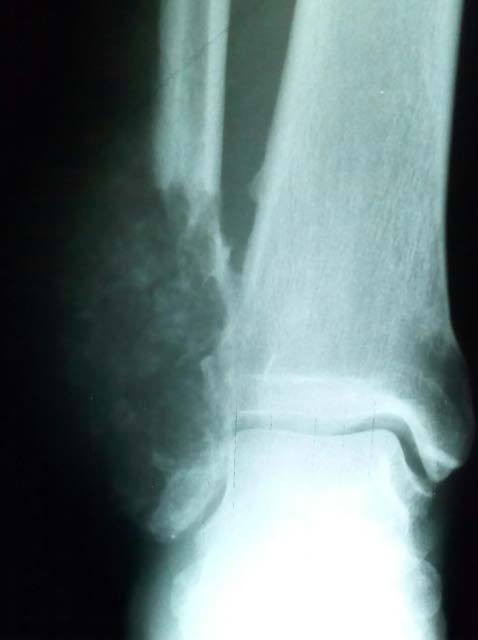

On examination, there was a 9 by 5 cm hard mass with hyper pigmented overlying skin (see fig. 1). The mass was nonpulsatile, nontender, non mobile, and was not fluctuant or warm. There were no ulcers, no evidence of surrounding oedema and no neurovascular deficits. The range of motion of the ankle and subtalar joints was limited.

Radiographs revealed an oval, expansile, lobulated cystic lesion. There was obvious soft tissue invasion laterally and medially, there was a thin peripheral sclerotic rim (see fig. 2).